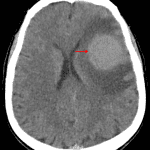

CT

- Rounded, hyperattenuating mass in the left frontal lobe with surrounding vasogenic edema